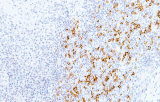

- Linfoma follicolare: tipici pattern di co-espressione (es. CD10 con BCL2 aberrante).

- LLC/LLS: co-espressione caratteristica di CD5 e CD23 nelle cellule B CD20+ (l'interpretazione richiede consapevolezza del pattern perché sono presenti cellule T reattive).

- Linfoma a cellule mantellari: ciclina D1 e SOX11 come marcatori chiave, incluso supporto per i casi ciclina D1 negativi.